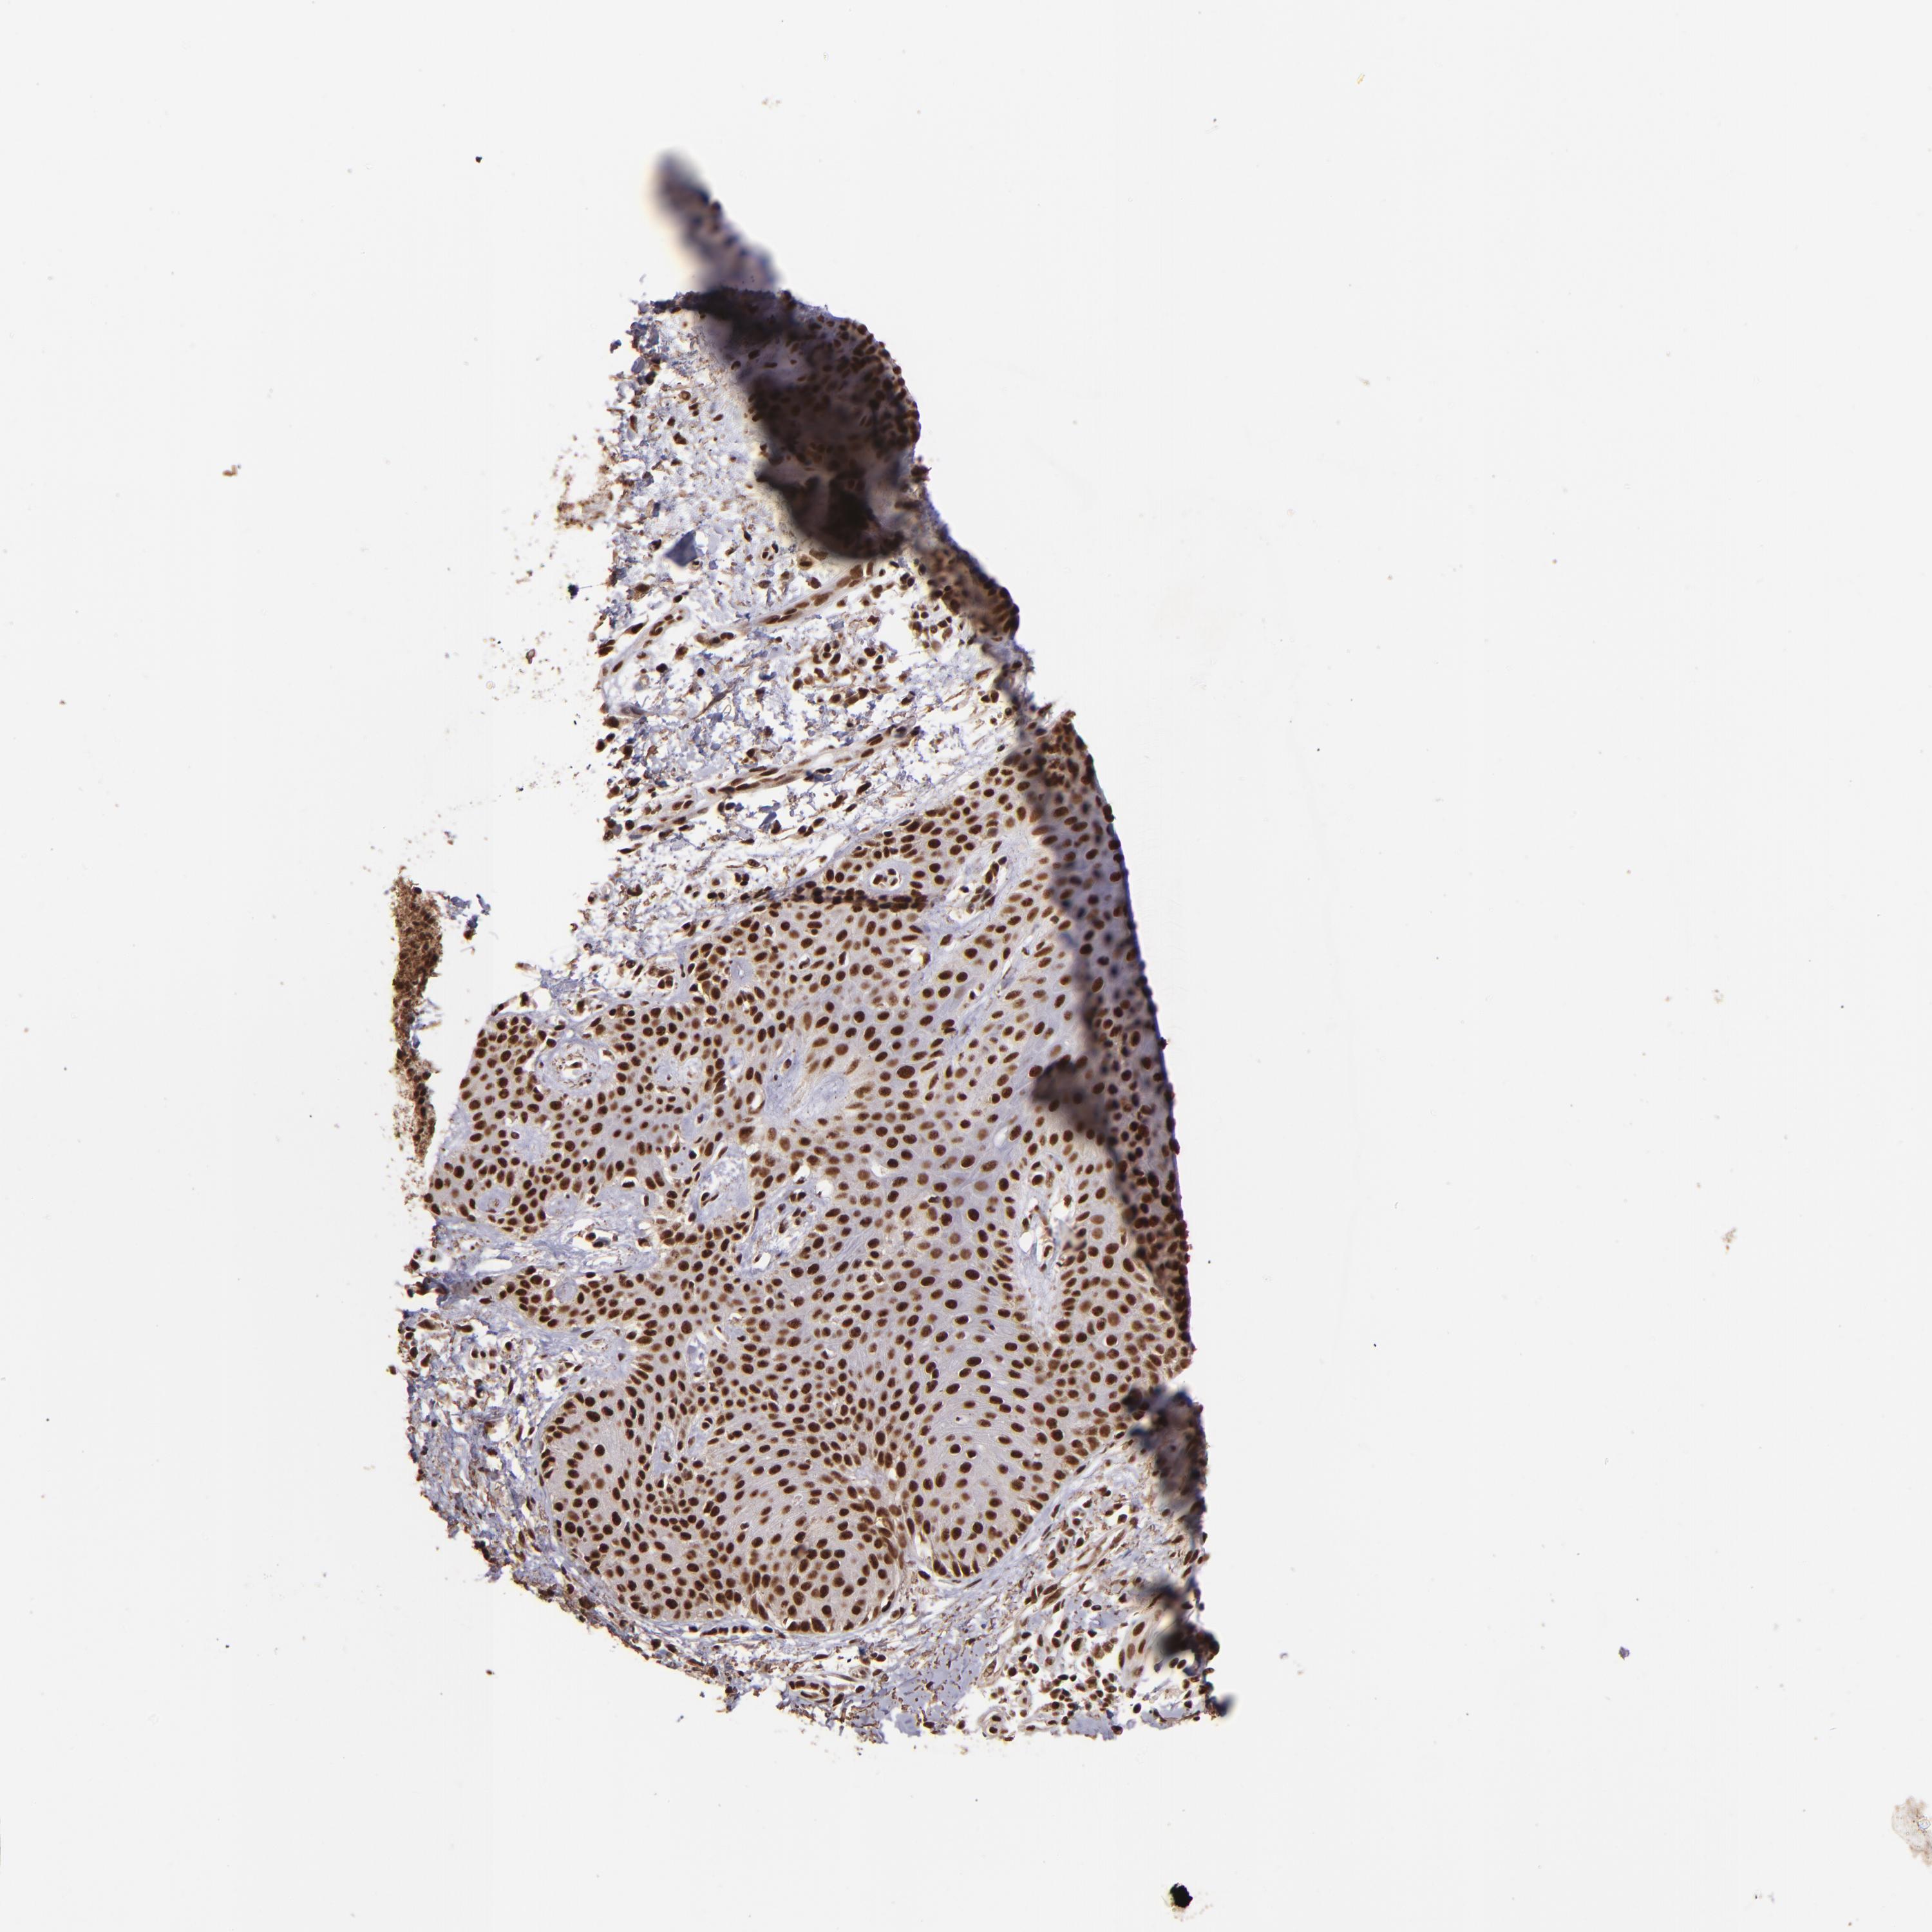

Basal cell and squamous cell cancer

SKIN CANCER - Protein expressioni

A mouse-over function shows sample information and annotation data. Click on an image to view it in a full screen mode. Samples can be filtered based on level of antibody staining by selecting one or several of the following categories: high, medium, low and not detected. The assay and annotation is described here.

Antibody stainingi

Antibody staining in the annotated cell types in the current human tissue is reported as not detected, low, medium, or high, based on conventional immunohistochemistry profiling in selected tissues. This score is based on the combination of the staining intensity and fraction of stained cells.

Each image is clickable and will lead to virtual microscopy that enables deeper exploration of all samples and also displays staining intensity scores, fraction scores and subcellular localization as well as patient and tissue information for each sample.

Antibody HPA001880

Staining

High

Intensity

Strong

Quantity

>75%

Location

Nuclear

Squamous cell carcinoma, NOS

Basal cell carcinoma